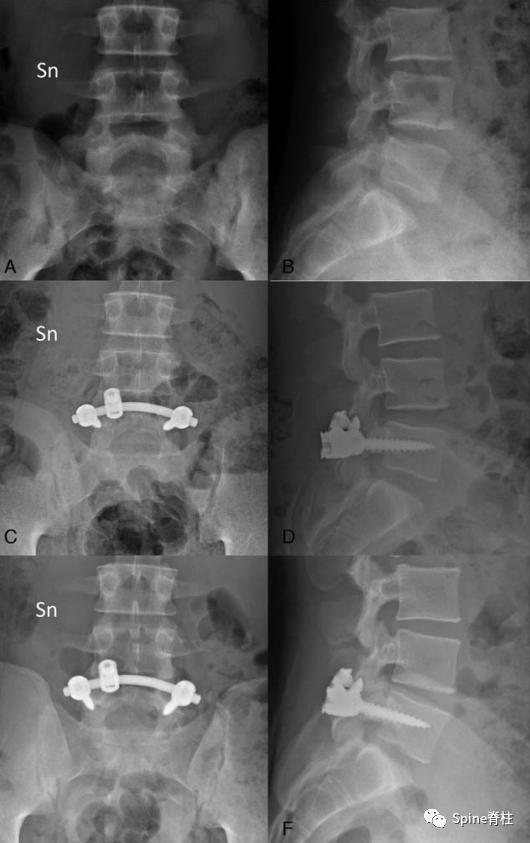

并建议保守治疗无效的青年战士A、B型腰椎峡部裂病例采用椎弓根螺钉固定,峡部自体髂骨原位植骨融合率高,效果好,C型战士峡部裂则宜采用后路椎间植骨融合椎弓根螺钉内固定术。

随着内固定的发展,既往峡部单纯修复植骨因融合率低、卧床时间长,现已很少应用。而植骨修复并节段固定有多种方法,包括Scott接线法、Buck螺钉法、Louis的蝶形板、钉钩技术(椎弓根螺钉和钩-棒系统)、U形棒等。从临床角度看,钉钩技术可以用刚性植入物固定断裂的峡部,并沿椎板方向施加作用力,有效稳定峡部,这对于达到更好的骨性愈合是至关重要的。理论上,此种方法更符合生物力学,对邻近节段影响小,但应把握好适应症,建议单纯腰椎峡部裂伴或不伴轻度滑脱患者可行植骨修复并节段固定。

1. 椎弓根螺钉-钉钩系统

PMID: 9199377

PMID: 15699811

PMID: 17520298